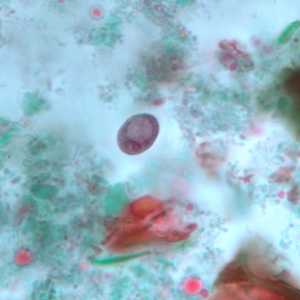

E. nana trophozoites stained with trichrome.

Figure A: Trophozoite of E. nana stained with trichrome.

Figure B: Trophozoites of E. nana stained with trichrome.

Figure C: Trophozoite of E. nana stained with trichrome.

Figure D: Trophozoite of E. nana stained with trichrome. Image courtesy of the Kansas Department of Health and Environment.

Figure E: Trophozoite of E. nana stained with trichrome.